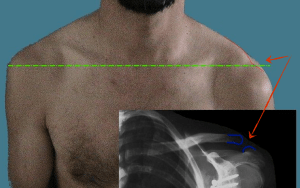

La luxation : outre la douleur locale, on observe une « touche de piano ».

Luxation ACL’entorse :

AC douleur locale

Le patient montre souvent la zone de lésion avec l’index de sa main opposée (pointing test)